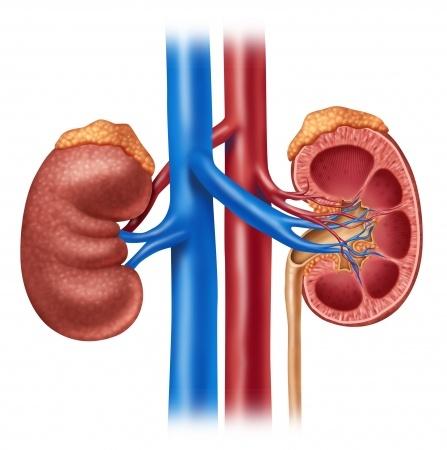

Az ilyen feleslegben bevitt fehérjék károsítják a veséket, drágák és lebomlásuk során cukrok képződnek belőlük. Drága módja a cukor pótlásnak a fehérje fogyasztás.

A húsok kéntartalmú aminosavakban igen gazdagok. Ezek az aminosavak létfontosak, de ha több van belőlük, akkor a szervezetünk lebontja ezeket. Első lépésben kénsav keletkezik belőlük, amik az anyagcsere folyamatok során gyorsan gyengébb savakra "cserélődnek" és a felesleges savak a vizelettel kiürülnek a szervezetünkből. Igen ám, de a vizelet savanyítása azzal a következménnyel jár, hogy megnő a kalcium kiválasztás is a vizeletben, ami a kalcium tartalmú vesekövesség kialakulására hajlamosít. A vesekövek több mint 80%-a a kalcium valamilyen sója.

Ha ezt el akarjuk kerülni, akkor csökkentenünk kell a húsfélék fogyasztást. A felnőtt ember napi fehérje igénye testsúly kilogrammonként 0,6-0,8g. Tehát egy 10 dkg-os hússzelettel bőven fedeztük napi fehérje igényünket.